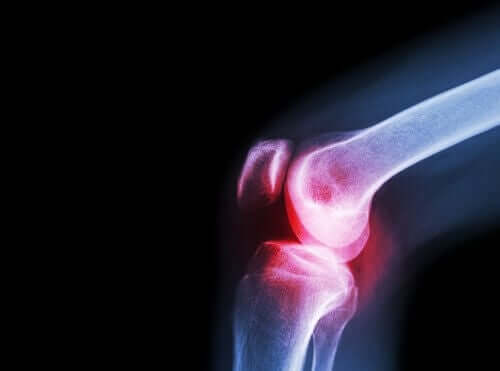

Voici une autre maladie pour laquelle l’acéclophénac est indiqué. C’est également une pathologie rhumatismale qui endommage le cartilage des articulations.

A l’intérieur des articulations, il y a un fluide que l’on appelle liquide synovial, produit par la membrane synoviale. Les extrémités des os qui se rejoignent pour former l’articulation sont recouverts par le cartilage articulaire.

Lorsque ce cartilage est blessé, des douleurs, des raideurs et une incapacité fonctionnelle apparaissent alors. Il est important de différencier cette maladie de l’arthrite. En effet, cette dernière a pour origine une inflammation de l’articulation et l’usure du cartilage.

Cependant, les deux sont douloureuses. Par conséquent, l’acéclophénac est efficace pour le traitement de ces différents symptômes.